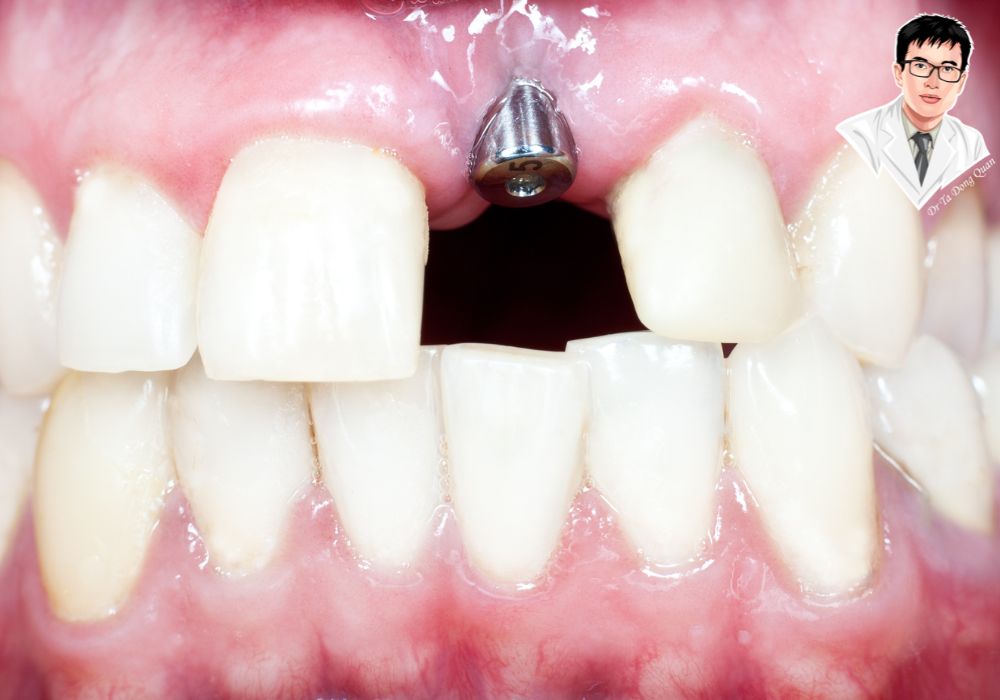

Chi phí trồng răng phụ thuộc rất lớn vào loại trụ implant được sử dụng. Đây là bộ phận quan trọng nhất của toàn bộ quy trình cấy ghép, đóng vai trò như chân răng nhân tạo để nâng đỡ mão sứ phía trên. Vì vậy, chất lượng trụ implant sẽ ảnh hưởng trực tiếp đến độ bền, khả năng tích hợp xương và tổng chi phí điều trị.

Trụ implant là phần được đặt trực tiếp vào xương hàm, đảm nhiệm chức năng thay thế chân răng thật. Nếu ví mão sứ là phần thân răng thì implant chính là nền móng. Do đó, sự khác biệt về vật liệu, công nghệ xử lý bề mặt hay nguồn gốc xuất xứ đều làm thay đổi chi phí đáng kể.